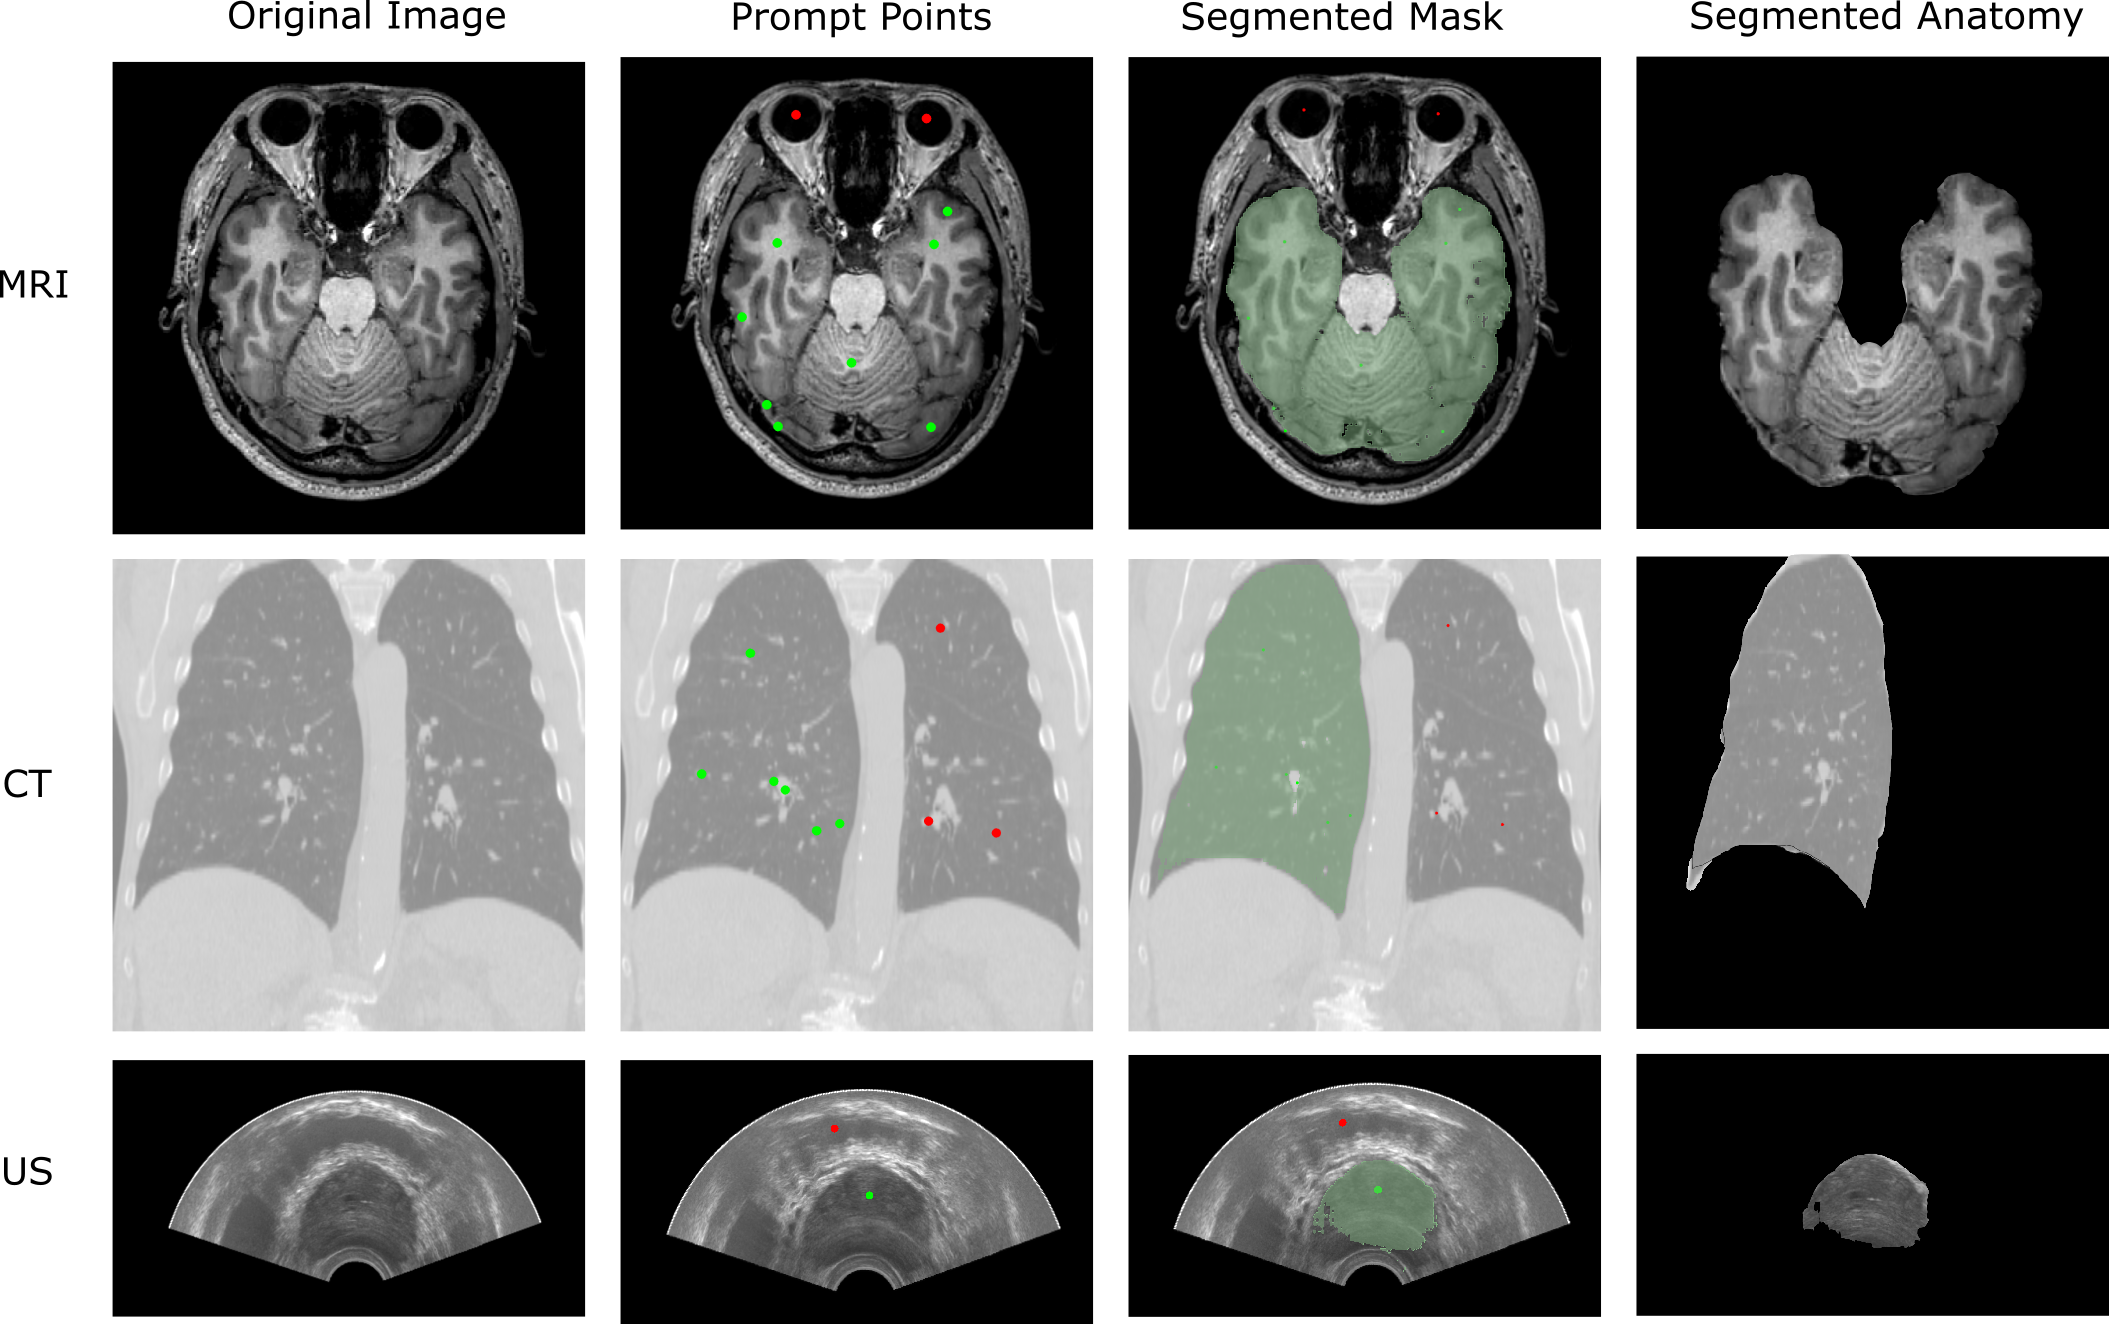

Refer to caption

Figure 3: Example results for different image formats (CT, MRI, and US). The prompts with green points are for the regions to be selected, whereas the red points are for the regions to be removed.

We evaluated the integration with SA-1B pre-trained model 111SA-1B is a model for SAM that is trained on 11 million diverse and high-resolution images and 1.1 billion high-quality segmentation masks (Kirillov et al., 2023) for different formats including CT, MRI, and US, using images with different anatomies. Figure 3 shows the manually placed prompts and the segmentation masks generated from the sample datasets of 3D Slicer. The Slicer-IPP provides a built-in markup tool for placing the prompt points. The segmentation mask is overlaid on the original image once the CPL_ INF task ends. All cases are tested in the same environment (Ubuntu 20.04, AMD Ryzen 9 3900X, Nvidia GeForce RTX 3090). The result demonstrates that SAM, although not specifically trained on medical image datasets, can generate masks for zero-shot segmentation tasks across different image formats.